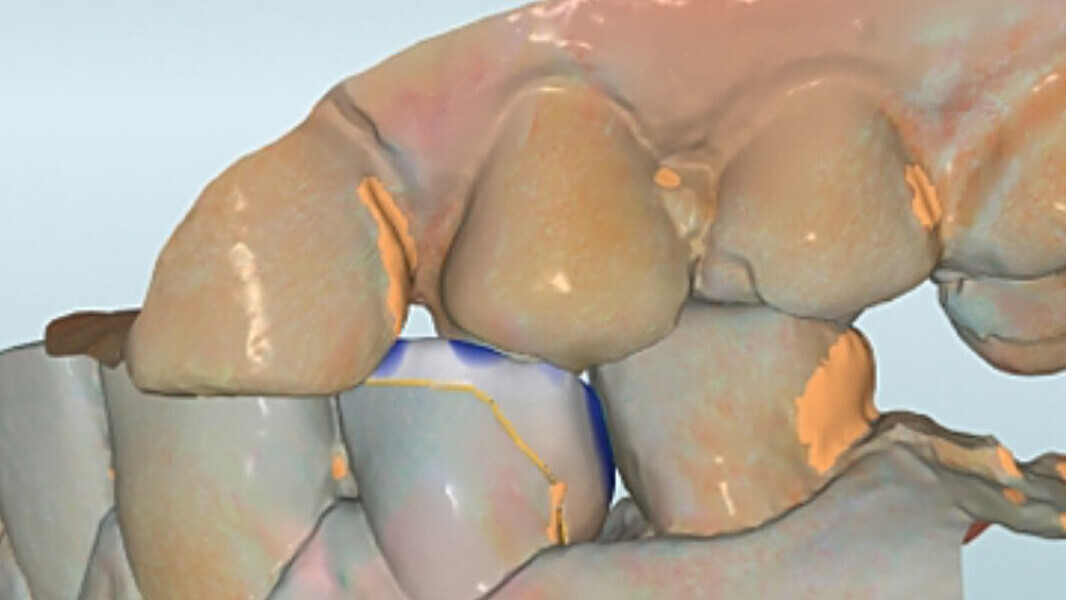

Fig. 6. Mediante un escaneo vestibular se trasladó la intercuspidación habitual.

Fig. 7. Durante el diseño de la restauración se respetaron los grosores de capa mínimos.